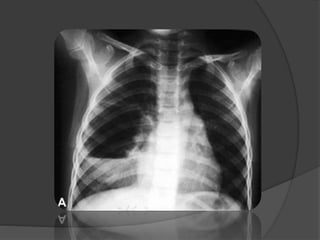

Imagerie

 La radiographie du thorax: Diagnostic (+)

Topographie

 Hyper clarté homogène compressive

 Trame vasculaire conservée mais grêle

 Signes de distension thoracique

 Hernie médiastinale + refoulement

controlatéral

 Pseudo-pneumothorax